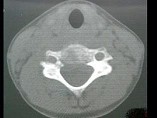

- 单项选择题男,37岁, 颈部疼痛,活动时加重, 休息可减轻,夜间有盗汗, 结合图像,最可能的诊断是 ( )

D、颈椎结核